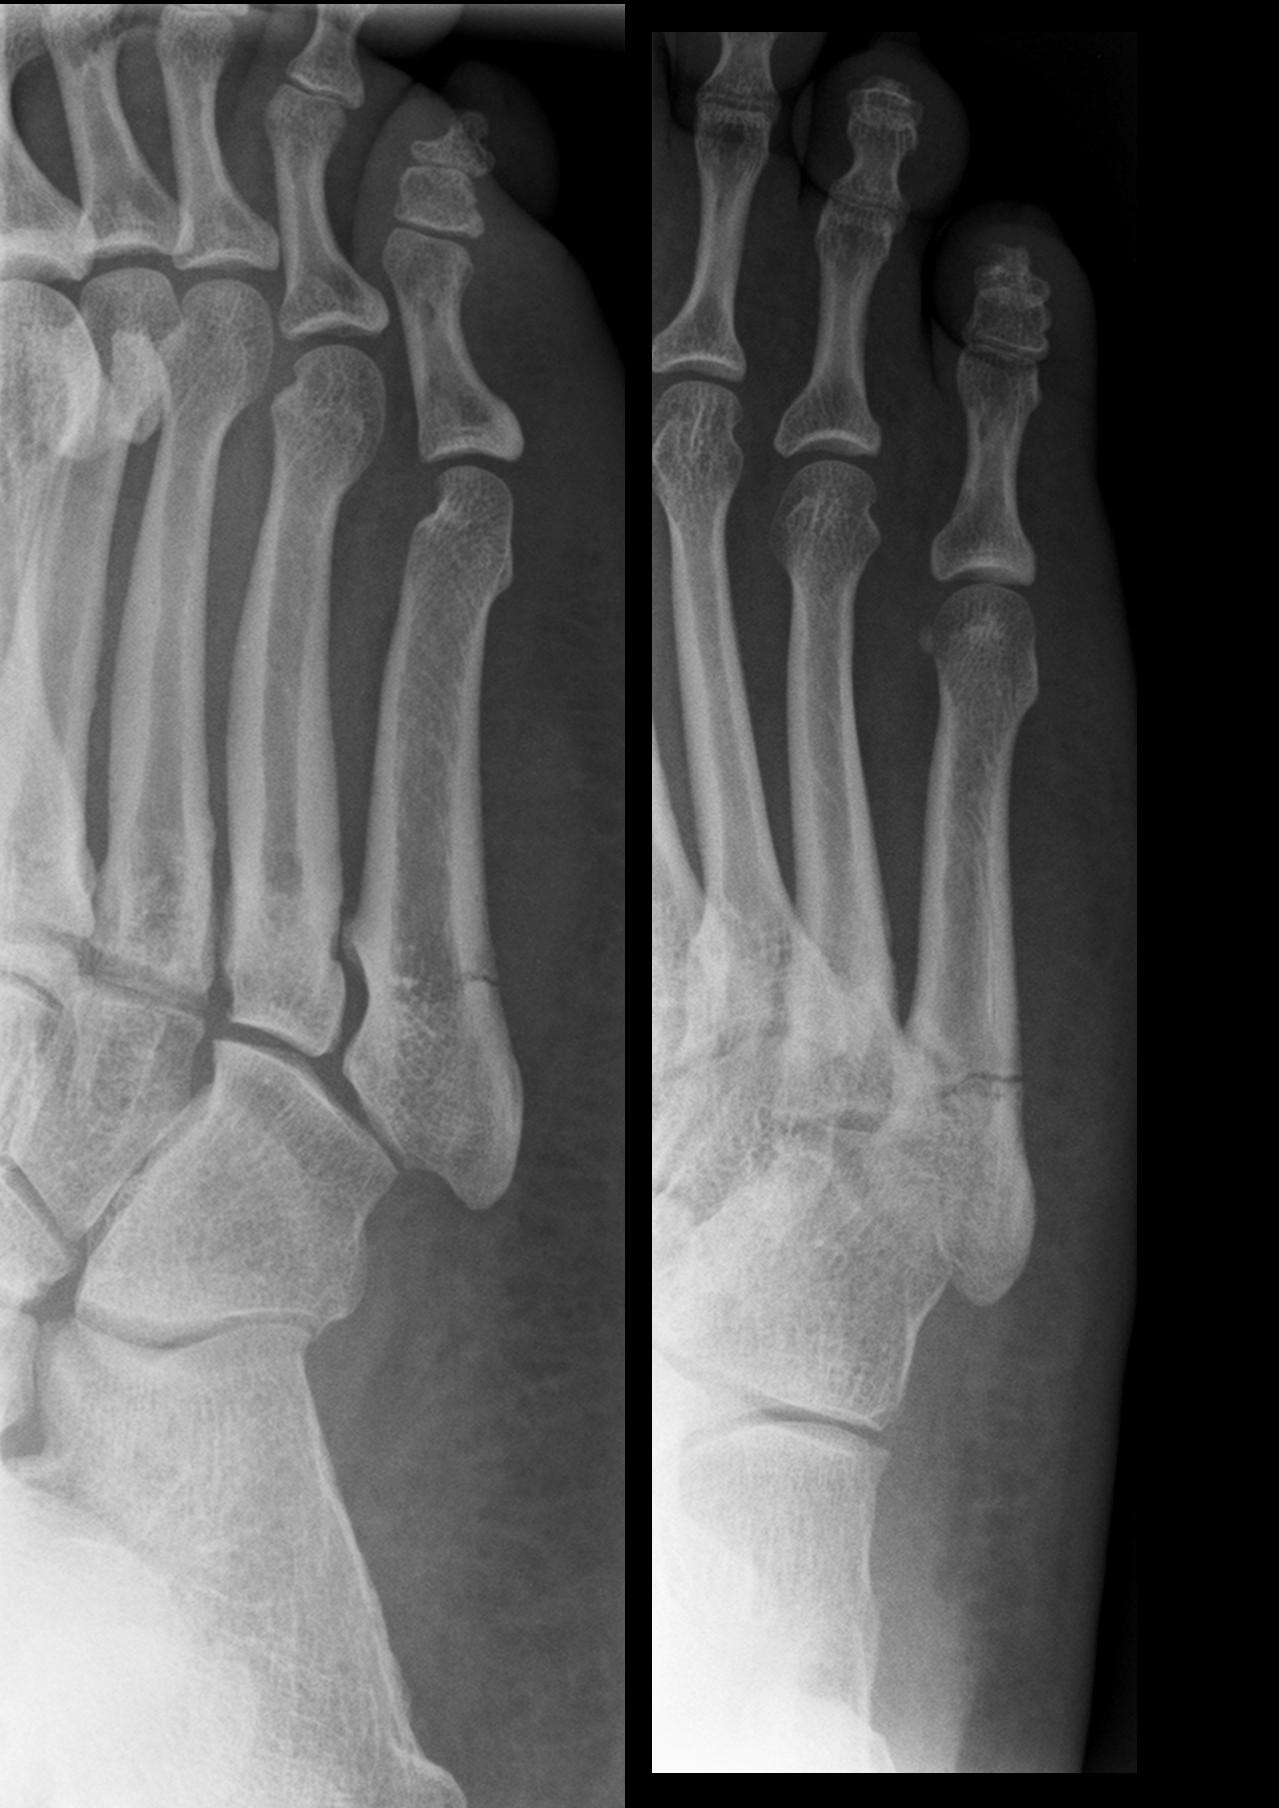

The Jones Fracture is named after a British Orthopaedic surgeon, Sir Robert Jones. He was the first to describe the fracture in the foot that occurs in the base of the 5th metatarsal bone on the lateral aspect of the foot. The fracture is thought to occur secondary to the accumulation of stress and pressure that is placed on that part of the 5th metatarsal. The compression and sheer forces that are placed on that part of the bone are enormous in some people and body weight and activity level can pre-dispose them to the Jones Fracture.

The bone accepts most of the body’s weight during gait and the Peroneus Brevis muscle inserts to that part of the metatarsal. The muscles strong contracting force to help stabilize the foot / ankle from the lateral side can increase the pressure applied to the base of the bone. The fractures are described by the area that they occur and it is one of three zones of the metatarsal. The first zone is a “chip” or avulsion fracture and treated conservatively in a cast or boot. The fracture that occurs at the junction of the base and the shaft it is in zone 2 and it might be fixed surgically. Lastly, a fracture in the shaft or zone 3 can take a very long time to heal and is frequently treated by performing surgery.